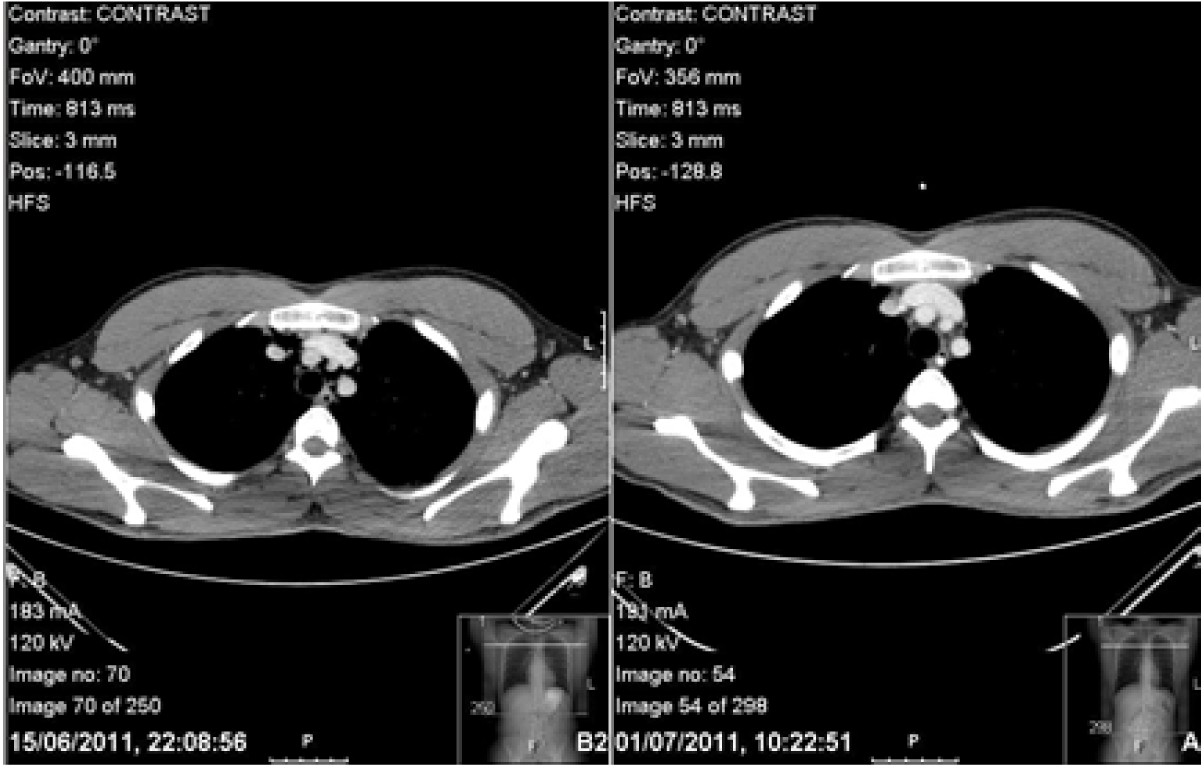

The patient’s symptoms returned spontaneously two days post discharge on the eve of his surgical finals. Subcutaneous emphysema was found on examination. Observations, blood tests and arterial blood gas (ABG) showed no abnormality. Computed tomography scan of chest with IV contrast and Gastrografin swallow showed pneumomediastinum but no leak of Gastrografin. (Figure 2) (Figure 3) Furthermore, there was the dilemma of whether he would be able to sit his exam which was at the same tertiary centre. He was given a stat bag of intravenous fluids, the aforementioned intravenous antibiotics, kept nil by mouth and allowed home to rest. He was admitted directly after his surgical finals and treated conservatively. Nutritional support was given via a nasogastric tube which was inserted under radiological guidance. The patient’s symptoms improved and a Gastrografin swallow study on day-10 was normal. Soft diet was commenced which he tolerated. The patient’s second hospital stay was 12 days. He continued with a fork mashable soft diet until his three month follow-up, which was satisfactory, returning to a normal diet thereafter. Thankfully, the patient passed his finals and continues to work as a doctor. (Figure 4) (Figure 5)

Figure 5: Computed tomography scan of chest with Gastrografin contrast; a comparison of image on admission image after resolution showing no surgical emphysema.